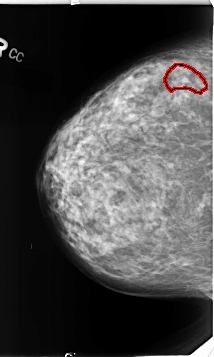

B_3133_1.RIGHT_CC

RIGHT_CC LINES 4632 PIXELS_PER_LINE 2776 BITS_PER_PIXEL 12 RESOLUTION 50 OVERLAY

FILE: B_3133_1.RIGHT_CC.OVERLAY

TOTAL_ABNORMALITIES 1

ABNORMALITY 1

LESION_TYPE CALCIFICATION TYPE PLEOMORPHIC DISTRIBUTION CLUSTERED

ASSESSMENT 4

SUBTLETY 2

PATHOLOGY BENIGN

TOTAL_OUTLINES 1

BOUNDARY